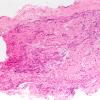

10A1 Neuroma (Case 10) H&E 4X